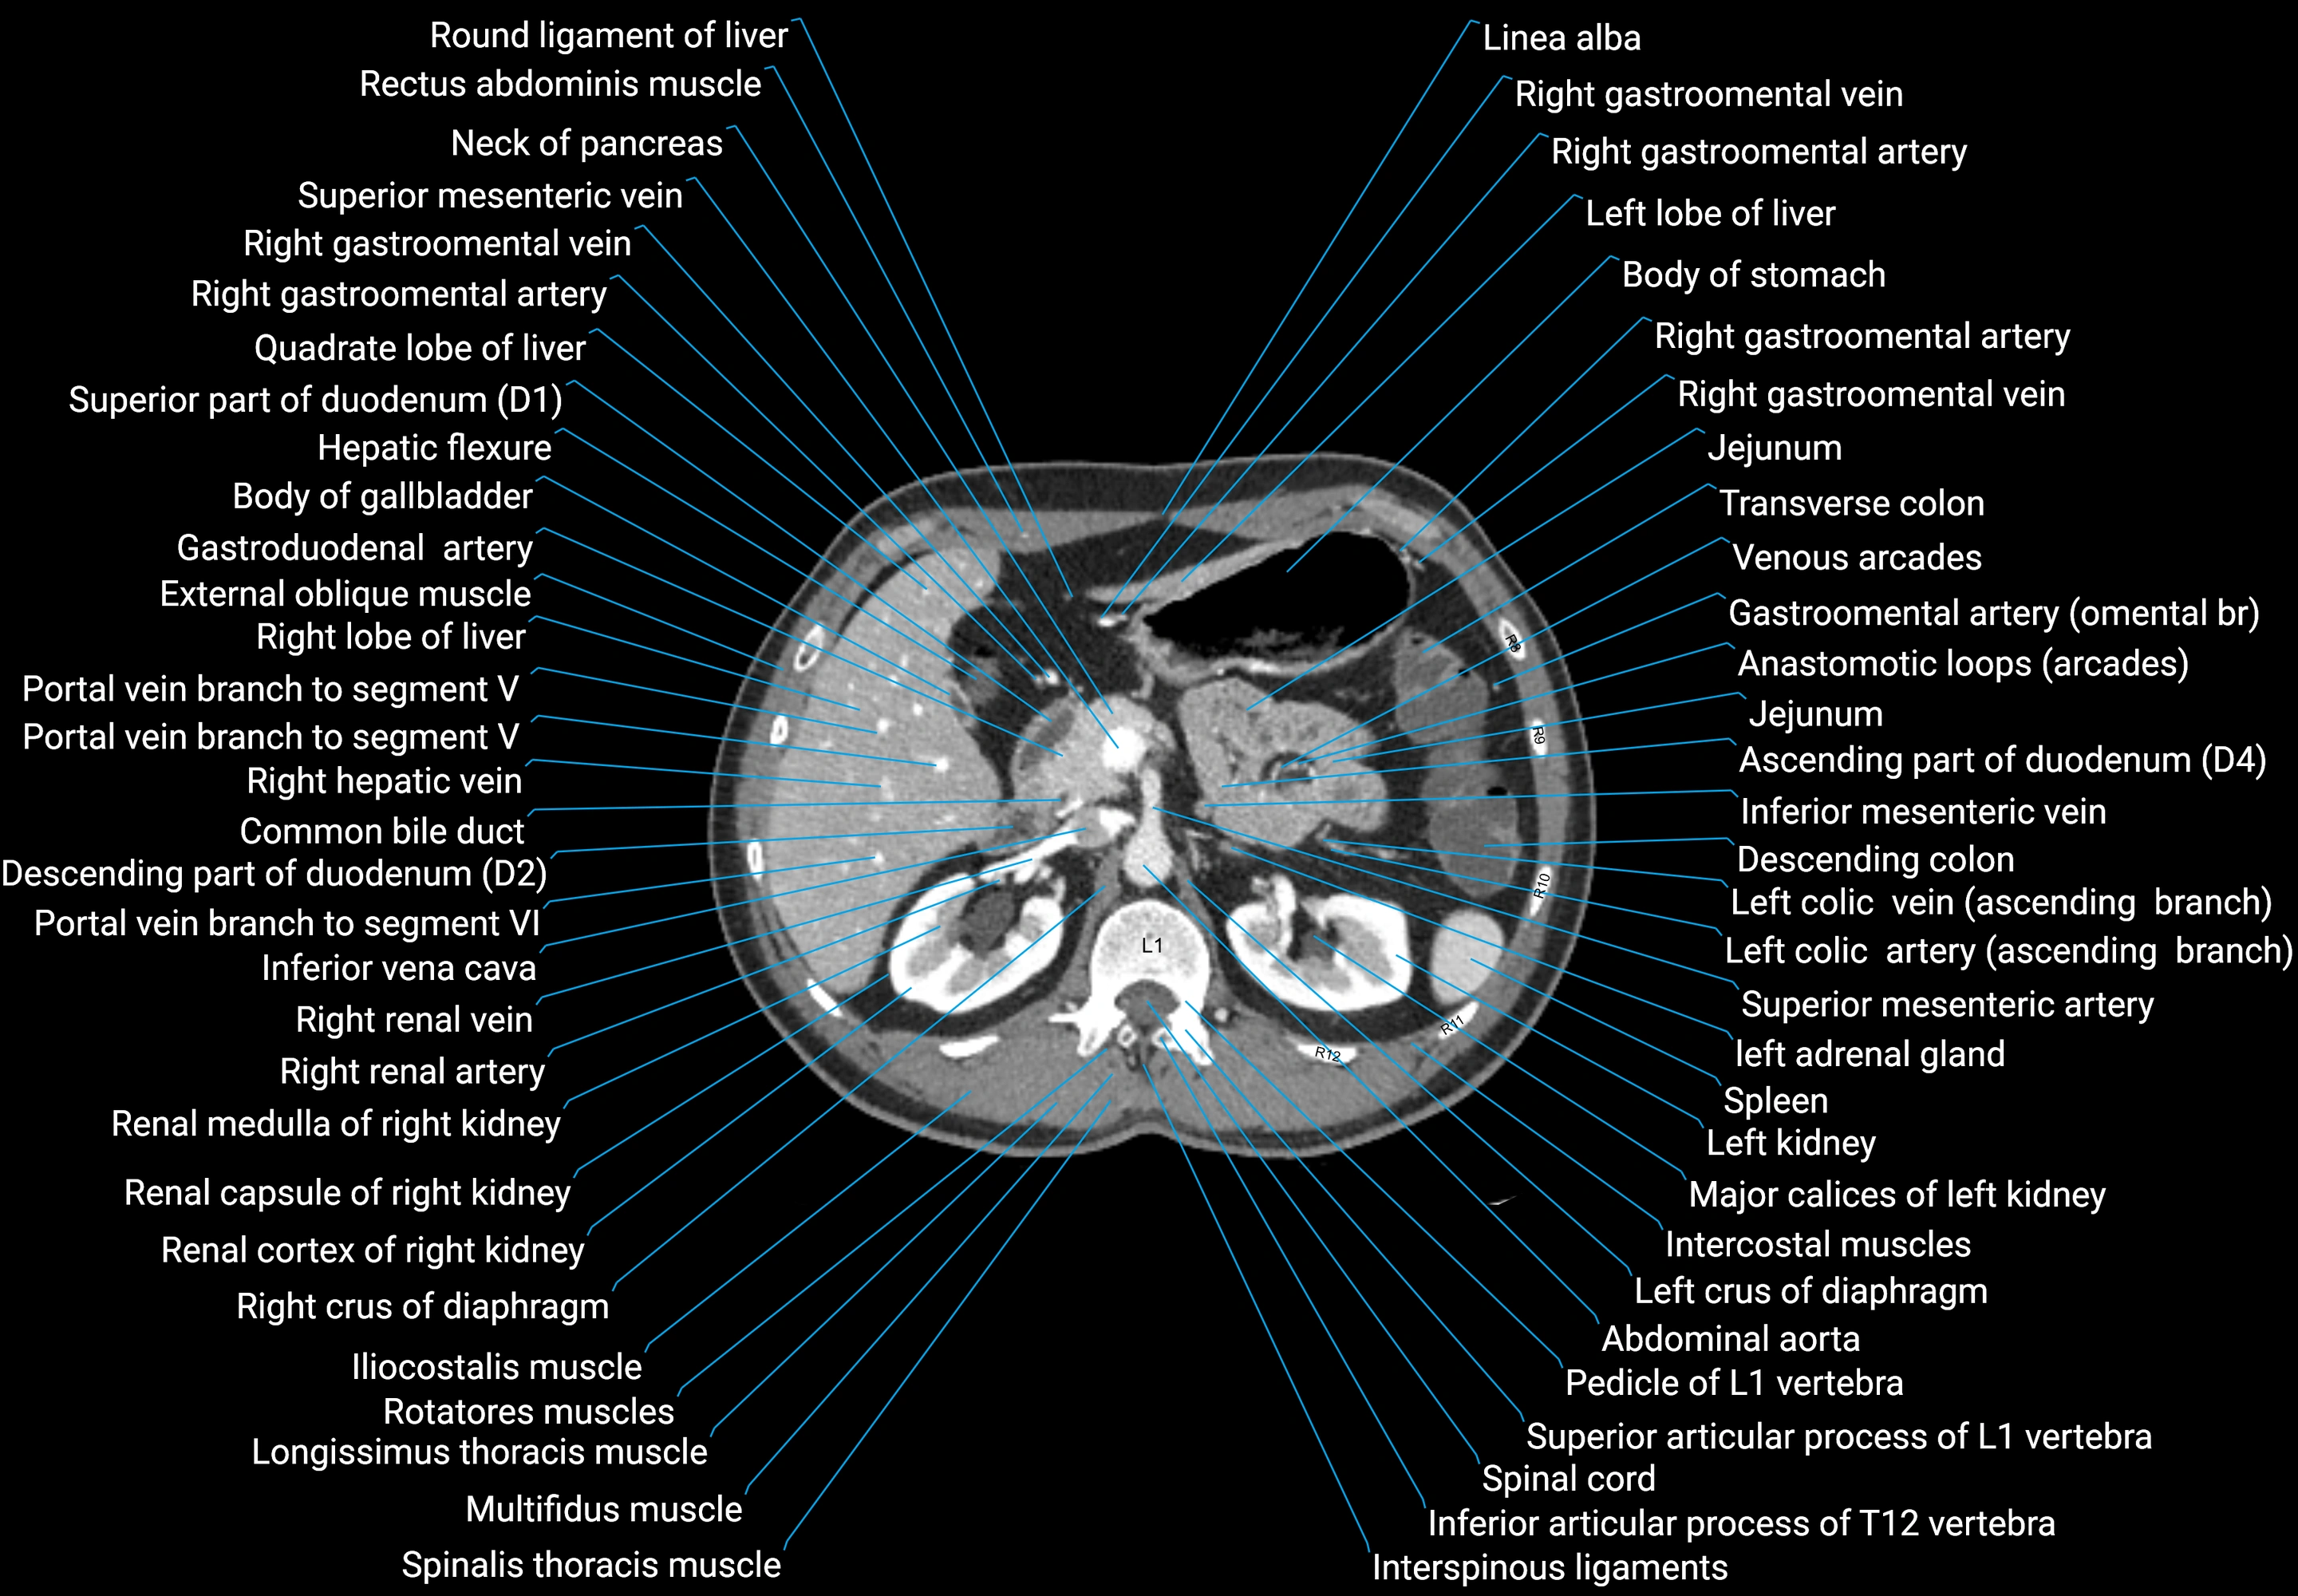

CT images